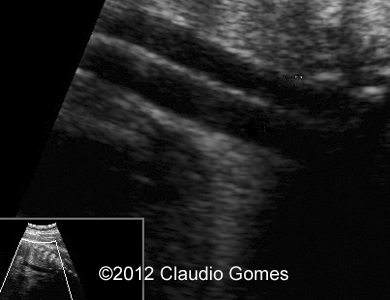

Image 2: Routine transverse view of the abdomen and thorax showing a vessel posterior and to the right of the aorta (Azygos vein).

Fig3